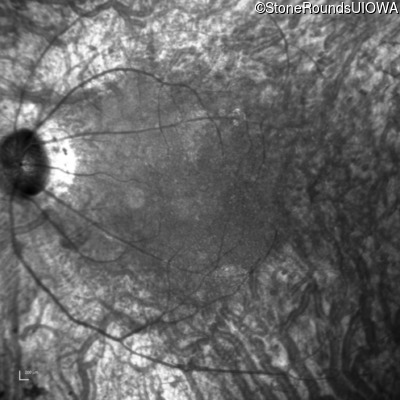

Infrared Fundus Photograph - Left - 20/80 -2

Exemplar